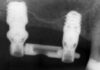

Ritrattamento canalare. Rimozione di 2 perni in fibra con tecnica ultrasonica

Il ritrattamento canalare è una procedura che si attua al fine di risolvere le problematiche endodontiche in essere e ha come scopo quello di...